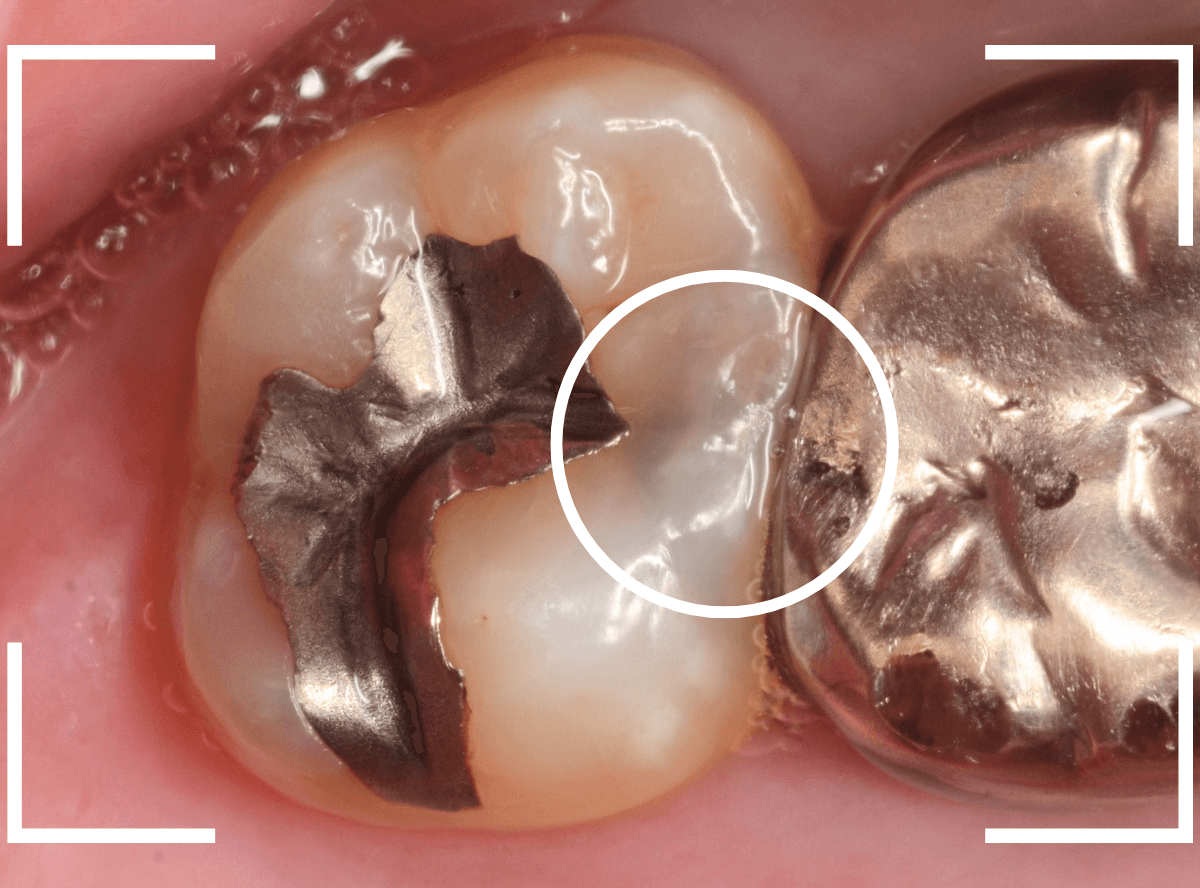

Case.25 レントゲン所見と目視を頼りに、虫歯治療

検査時に〇部、歯と歯の間の小臼歯部に虫歯らしき黒い影があるのが見つかりました。

かなり怪しいですが、メタル・インレーが入ってるので、それが透けている可能性もあります。

レントゲン写真で確認します。

レントゲンでは後ろの大臼歯部の方が虫歯になっているように見え、小臼歯部は問題ないように見えます。

まず大臼歯のインレーを外して、中を調べます。

あれ、インレー直下は虫歯がなさそうです。

レントゲン写真を頼りに、歯を削ると、虫歯が出てきました。

大臼歯の虫歯を削っていくと、手前の小臼歯まで虫歯がつながっていました。

やはり、黒い影は虫歯でした。これは深そうです。

メタル・インレーも外して、虫歯を除去します。

全ての虫歯を除去しました。

レントゲン写真では確認できませんでしたが、手前の小臼歯は深い虫歯でした。

このように、歯と歯の間の虫歯は、深い事が多いです。